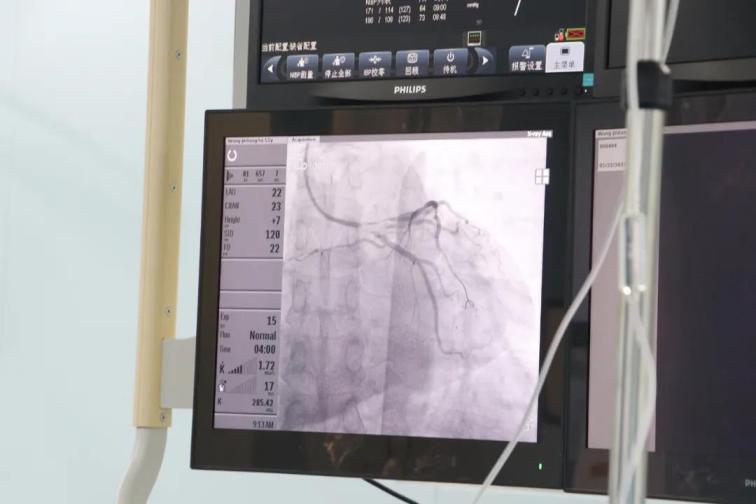

患者王某,男性,52歲,因胸悶半年,加重伴呼吸困難6天于5月8日入院,否認(rèn)高血壓和糖尿病史,外院256排CT提示:左前降支近段局限性中度狹窄,不能完全排除重度可能。入院后行心臟冠狀動脈造影檢查,結(jié)果提示前降支近段狹窄90%,中段狹窄70%,合并心肌橋,遠(yuǎn)段狹窄80%,患者及家屬不接受植入支架,在給予前降支近段充分預(yù)處理后,使用藥物涂層球囊送至病變部位,緩慢加壓,持續(xù)擴(kuò)張45秒,術(shù)后患者癥狀消失,并于5月27日痊愈出院。